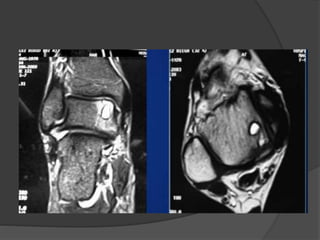

LESIONES

OSTEOCONDRALES

EPIDEMIOLOGÍA

 1% del total de fracturas astragalinas.

 75% son diagnosticadas como esguince de

tobillo.

 Presentes en 5% de esguinces de tobillo.

 Anterolaterales

 Posteromediales

tratamiento

 Lesiones agudas sin desplazamiento, deben

inmovolizarce

 Reposición del fragmento

 Curetaje (no mayores de 1cm)

 Transporte osteocondral (mayores a 1 cm)

 Tratamiento artroscopico